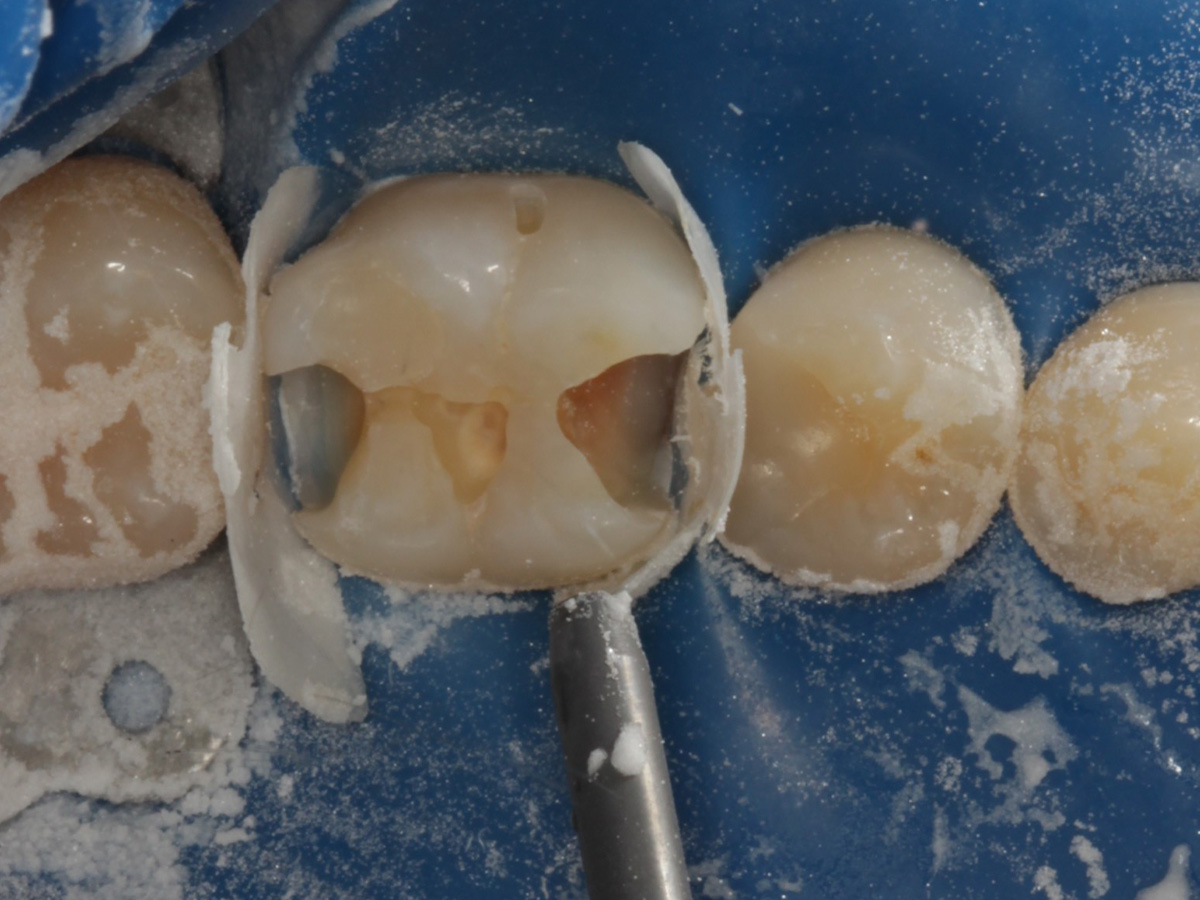

Abbildung 4

Defektdarstellung; „Schutzmatrizen“ ideal als „Leitplanken“ bei der Zahnpräparation tief approximal bis in gesunde Zahnsubstanz